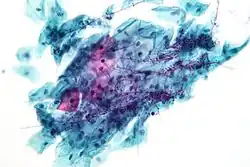

Squamous metaplasia of the cervix, with typical features. Pap stain.

Pap tests commonly examine epithelial abnormalities, such as metaplasia, dysplasia, or borderline changes, all of which may be indicative of CIN. Nuclei will stain dark blue, squamous cells will stain green and keratinised cells will stain pink/ orange. Koilocytes may be observed where there is some dyskaryosis (of epithelium). The nucleus in koilocytes is typically irregular, indicating possible cause for concern; requiring further confirmatory screens and tests.